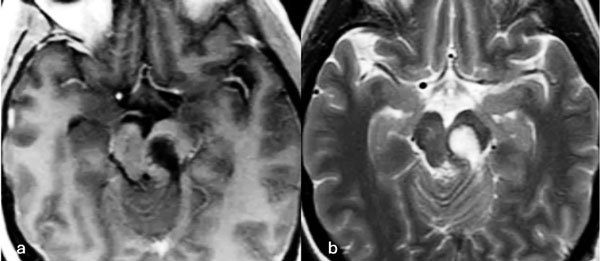

Figura 9. RM preoperatoria de encéfalo. Se evidencia una lesión única intraaxial bulbotrigonal izquierda, que contacta la mitad inferior del piso del cuarto ventrículo, hiperintensa en T1 y T2, con vacíos de flujo que impresionan provenir de una malformación del desarrollo venoso, lo que sugiere una malformación cavernomatosa. A) Imagen en corte sagital ponderada en T1 posterior a la administración de gadolinio. B y C) Imágenes en corte axial ponderadas en T1 y T2, respectivamente.

Figura 10. Imágenes intraoperatorias bajo microscopía. Craneotomía suboccipital de línea media, con abordaje intertonsilar. A) Abordaje intertonsilar con disección telovelar hacia la derecha, abriendo el techo del cuarto ventrículo. B) Protrusión e identificación de la cápsula del cavernoma en relación al piso del cuarto ventrículo. C) Resección en bloque de la malformación cavernomatosa. D) Revisión del lecho, sin remanente.